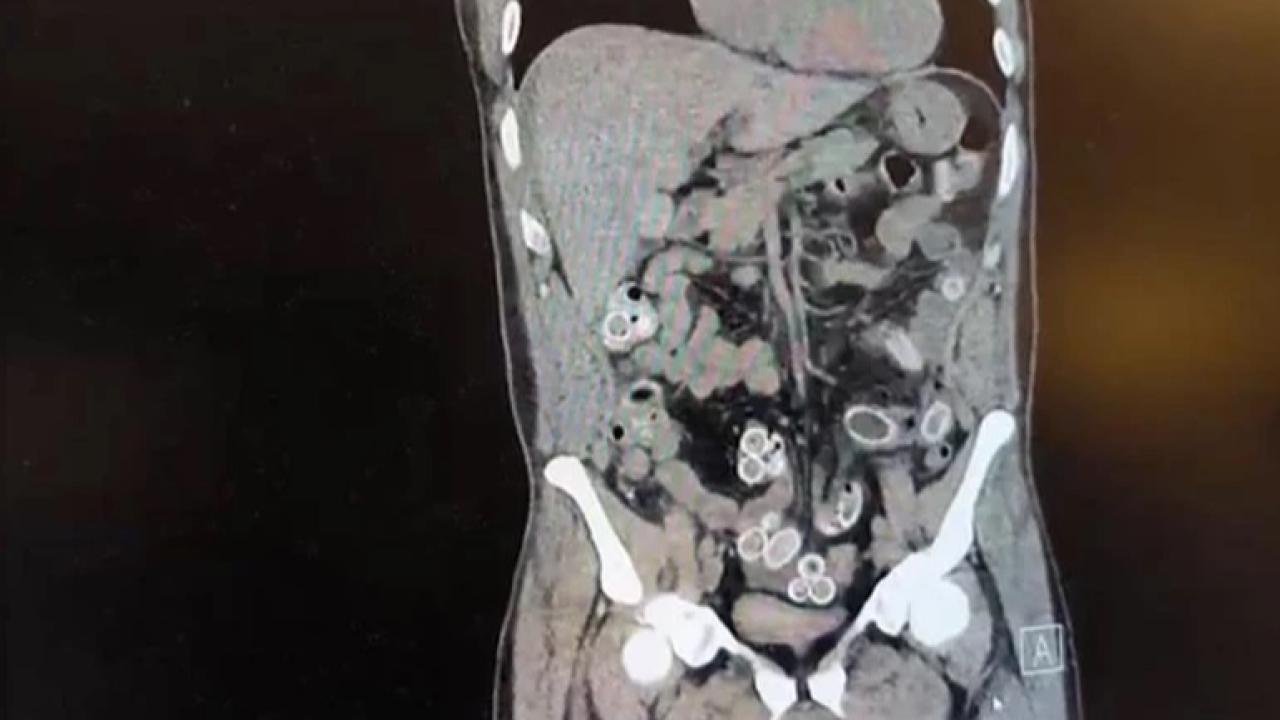

İstanbul Beşiktaş’ta yaşanan olayda, Fas’tan uçakla Türkiye’ye gelen 52 yaşındaki Cüneyt Ç., gelişinden iki gün sonra şiddetli karın ağrısı nedeniyle hastaneye başvurdu. Fulya’da bulunan özel bir hastanede yapılan tetkiklerde, şüphelinin mide ve bağırsaklarında şüpheli maddeler olduğu belirlendi.

Doktorların durumu fark etmesi üzerine hastane yönetimi polis ekiplerine bilgi verdi. İhbarın ardından Beşiktaş Asayiş Büro Amirliği ekipleri hastaneye gelerek inceleme başlattı. Yapılan değerlendirme sonrası ameliyata alınan Cüneyt Ç.’nin mide ve bağırsaklarından kapsül halinde gizlenmiş 49 adet esrar macunu çıkarıldı. Uyuşturucu maddelerin toplam ağırlığının yaklaşık 260 gram olduğu öğrenildi. Ayrıca şüpheliye ait bir cep telefonu da polis ekiplerine teslim edildi.

Fas’tan Türkiye’ye geldikten iki gün sonra karın ağrısıyla hastaneye giden 52 yaşındaki şahıs, midesinden çıkarılan 49 kapsül esrar macunu sonrası tutuklandı.